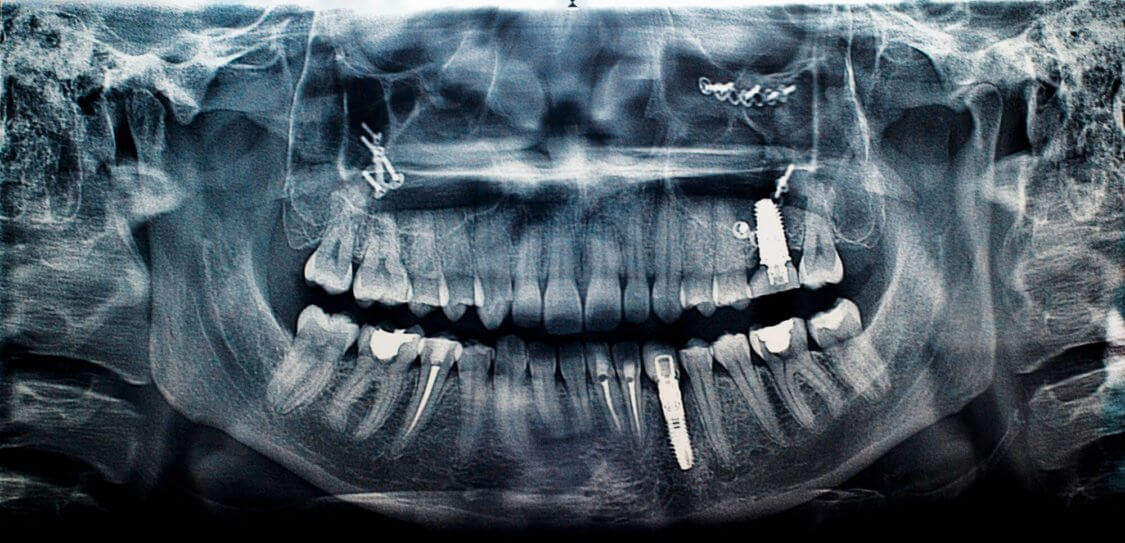

La mucositis y periimplantitis son enfermedades periodontales que afectan a las personas con implantes dentales.

En primer lugar, la periimplantitis es la enfermedad inflamatoria alrededor del hueso que sostiene un implante. Está producido por una infección bacteriana y favorecida por una serie de factores de riesgo como el alcohol o el tabaco. Su manifestación más evidente es la pérdida de hueso y suele estar asociada a una inflamación adicional de los tejidos blandos circundantes. Por otro lado, la mucositis es la reacción inflamatoria alrededor de los tejidos blandos que rodean a un implante dental. Se manifiesta normalmente con el sangrado de encías, enrojecimiento, y dolor.